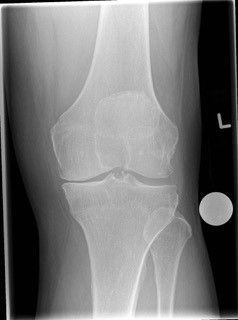

Arthritis of the knee currently affects approximately 8.5 million people in the UK, with one in five adults over 45 years old having symptoms that affect their daily life. These symptoms can range from intermittent discomfort and an occasional knee swelling at lower intensities, to constant pain with marked joint deformity, stiffness, instability, and resultant falls at higher intensities. So how does one know if the early symptoms of possible knee arthritis need treatment? Is there anything that can be done to prevent or slow down progression of knee arthritis? What are the latest treatment developments?

An expert assessment of your knee combined with some simple X-rays and scans can reveal in great detail the overall health of your knee joint and will also allow a personalised discussion about what treatments are suitable for your needs. Not all people with knee niggles require interventional or surgical treatment, but if they do, then a number of options can be discussed, from “keyhole” surgery for minor issues up to knee replacement for established arthritis. For individuals who only have arthritis affecting one of the three knee compartments, then most would be suitable for a partial knee replacement. Hospital stays are typically very short (usually one night) or even day case. The outcomes of partial knee replacement are excellent, patients often experience a quicker return to normal function and can also participate in most sports and activities when rehabilitation is complete.